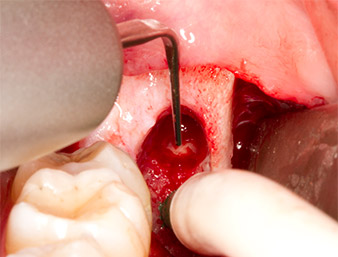

Sous bloc nerveux et anesthésie locale, le site d’intervention est ouvert et les tissus mous sont exposés afin d’accéder à la zone rétromolaire buccale (Fig. 3).

Le tissu recouvrant le reste radiculaire n’est pas entièrement ossifié et est essentiellement constitué de tissu de granulation modifié par l'inflammation (Fig. 4).